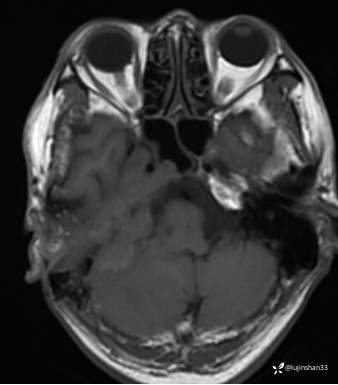

(2023-06-02 11:09,本院)磁共振(颅脑):1、右侧颞骨全切除术后改变,术区及相邻右侧斜坡、颞肌、咬肌、翼内外肌异常信号,考虑炎性肉芽肿性病变可能,请结合临床随诊复查;2、右侧小脑半球异常信号,考虑炎性病变可能;3、脑内散在缺血灶,软化灶形成;4、双侧蝶窦炎。

(2023-05-29 16:07,本院)CT颅脑:1、右侧颞骨全切除术后改变,术区见气体密度影,瘘管形成可能;术区多发软组织影,不完全除外炎性改变可能。2、左侧颞骨CT平扫未见明显异常。

是否应该补充诊断“小脑脓肿”?